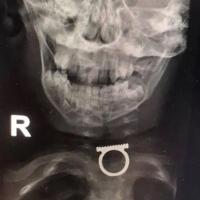

DEČAK SE ŽALIO NA BOL U USTIMA, a onda mu doktori PRONAŠLI PRSTEN KOD JEDNJAKA: "Hvala vam što ste spasili život mog sina!"